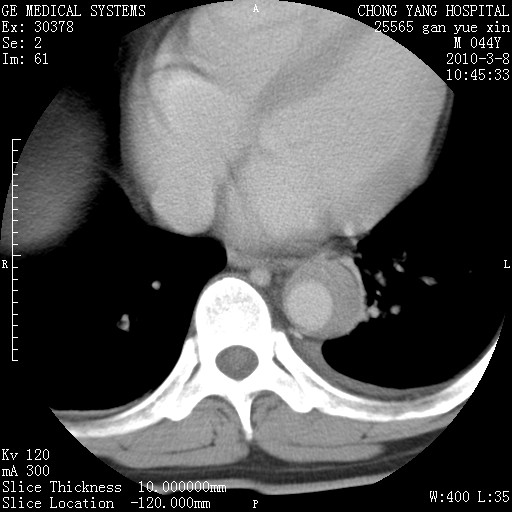

标题: CT24940:主动脉增强,典型病例。 [打印本页]

标题: CT24940:主动脉增强,典型病例。

夹层动脉瘤。

动脉夹层

夹层动脉瘤,典型

主动脉夹层。

动脉夹层的分型:

⒈debakey分型:根据主动脉夹层累及部位,分为三型:ⅰ型:原发破口位于升主动脉或主动脉弓部,夹层累及升主动脉、主动脉弓部、胸主动脉、腹主动脉大部或全部,少数可累及髂动脉。ⅱ型:原发破口位于升主动脉,夹层累及升主动脉,少数可累及部分主动脉弓。ⅲ型:原发破口位于左锁骨下动脉开口远端,根据夹层累及范围又分为ⅲa,ⅲb。ⅲa型:夹层累及胸主动脉。ⅲb型:夹层累及升主动脉、腹主动脉大部或全部。少数可累及髂动脉。

⒉stanford分型:a型:夹层累及升主动脉,无论远端范围如何。b型:夹层累及左锁骨下动脉开口以远的降主动脉。

夹层动脉瘤,少量胸水

夹层动脉瘤;左侧少量胸腔积液。

典型主动脉夹层。